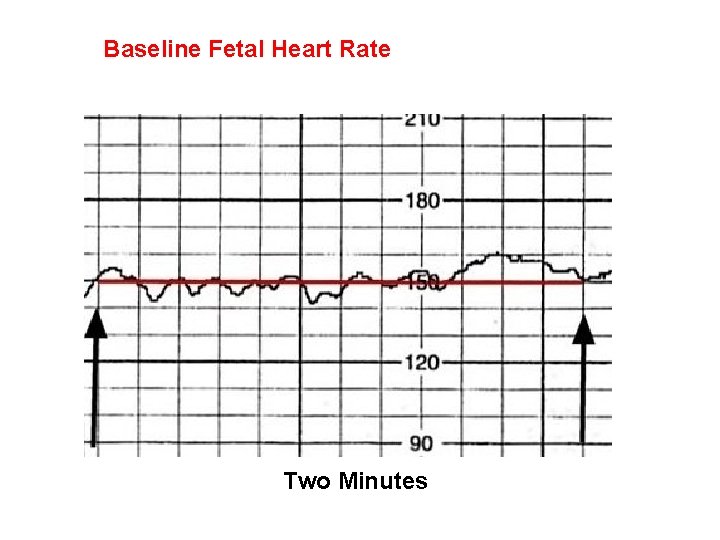

Baseline Fetal Heart Rate The baseline FHR is the heart rate during a 10 minute segment rounded to the nearest 5 beat per minute increment excluding periods of marked FHR variability, periodic or episodic changes, and segments of baseline that differ by more than 25 beats per minute. • The minimum baseline duration must be at least 2 minutes. • If minimum baseline duration is < 2 minutes then the baseline is indeterminate. • Normal baseline = 110 -160 bpm

Baseline Fetal Heart Rate Two Minutes